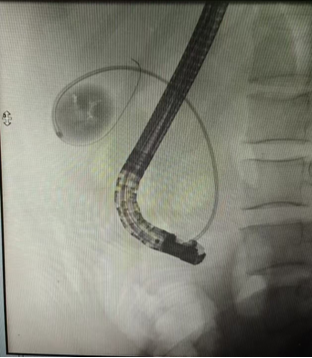

针对张先生的病情,该院消化内科胆胰疾病亚专业组主任医师张利、副主任医师屈重行牵头,联合门诊麻醉、内镜护理团队,决定采用 ERCP 联合经口胆道镜胆囊结石取石术这一创新方案。

第一步,借助内镜逆行胰胆管造影术(ERCP)清除胆总管内结石,解除胆道梗阻;

第二步,经口胆道镜精准进入胆囊腔,用一次性取石网篮抓取多发小结石;

第三步,通过子镜反复注水、抽吸,清理胆囊腔内残留沉积物,确保胆囊内部洁净。